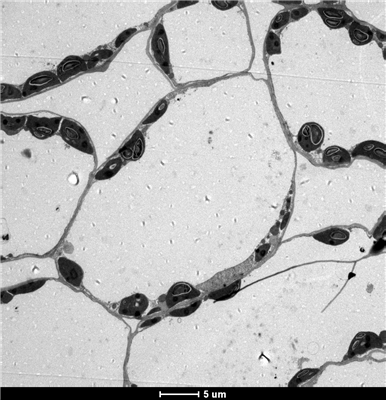

透射電鏡H-7650是一臺高分辨率成像儀器,使用雙狹縫物鏡,可以得到獨有的低倍大視野,高對比度成像的特點,配有高靈敏度CCD相機,具有低劑量電子束成像的功能;具有更多的自動化功能,如自動聚焦,自動消像散,自動拍照等;具有圖像數據功能,測長,圖像過濾功能,具有較強的拓展功能。

6.超薄切片機切片(50-60 nm)

7.3%醋酸鈾-枸櫞酸鉛雙染色

8.透射電鏡觀察,拍片